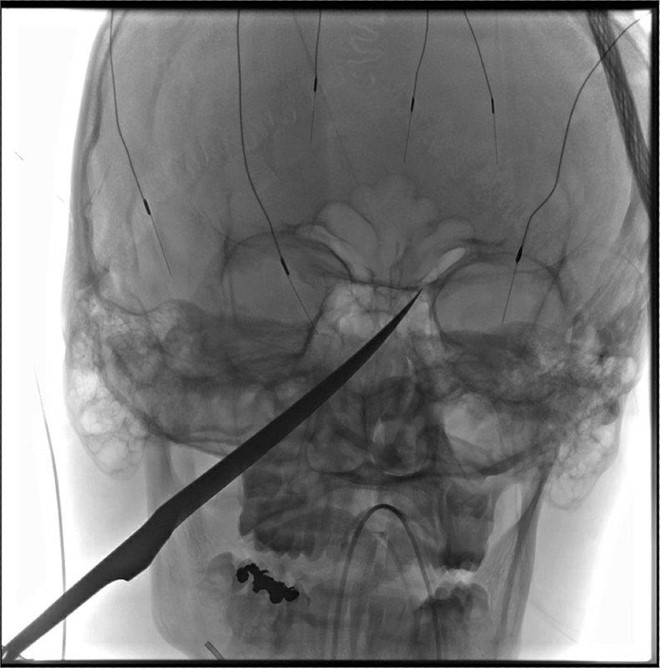

Lưỡi dao đã đâm xuyên vào hộp sọ và suýt chạm tới não của Gregg. Mũi dao khi đó gần chạm tới động mạch cảnh, nơi cung cấp máu cho não, theo AP.

Hình chụp X-quang hộp sọ của Eli Gregg. Ảnh: AP.